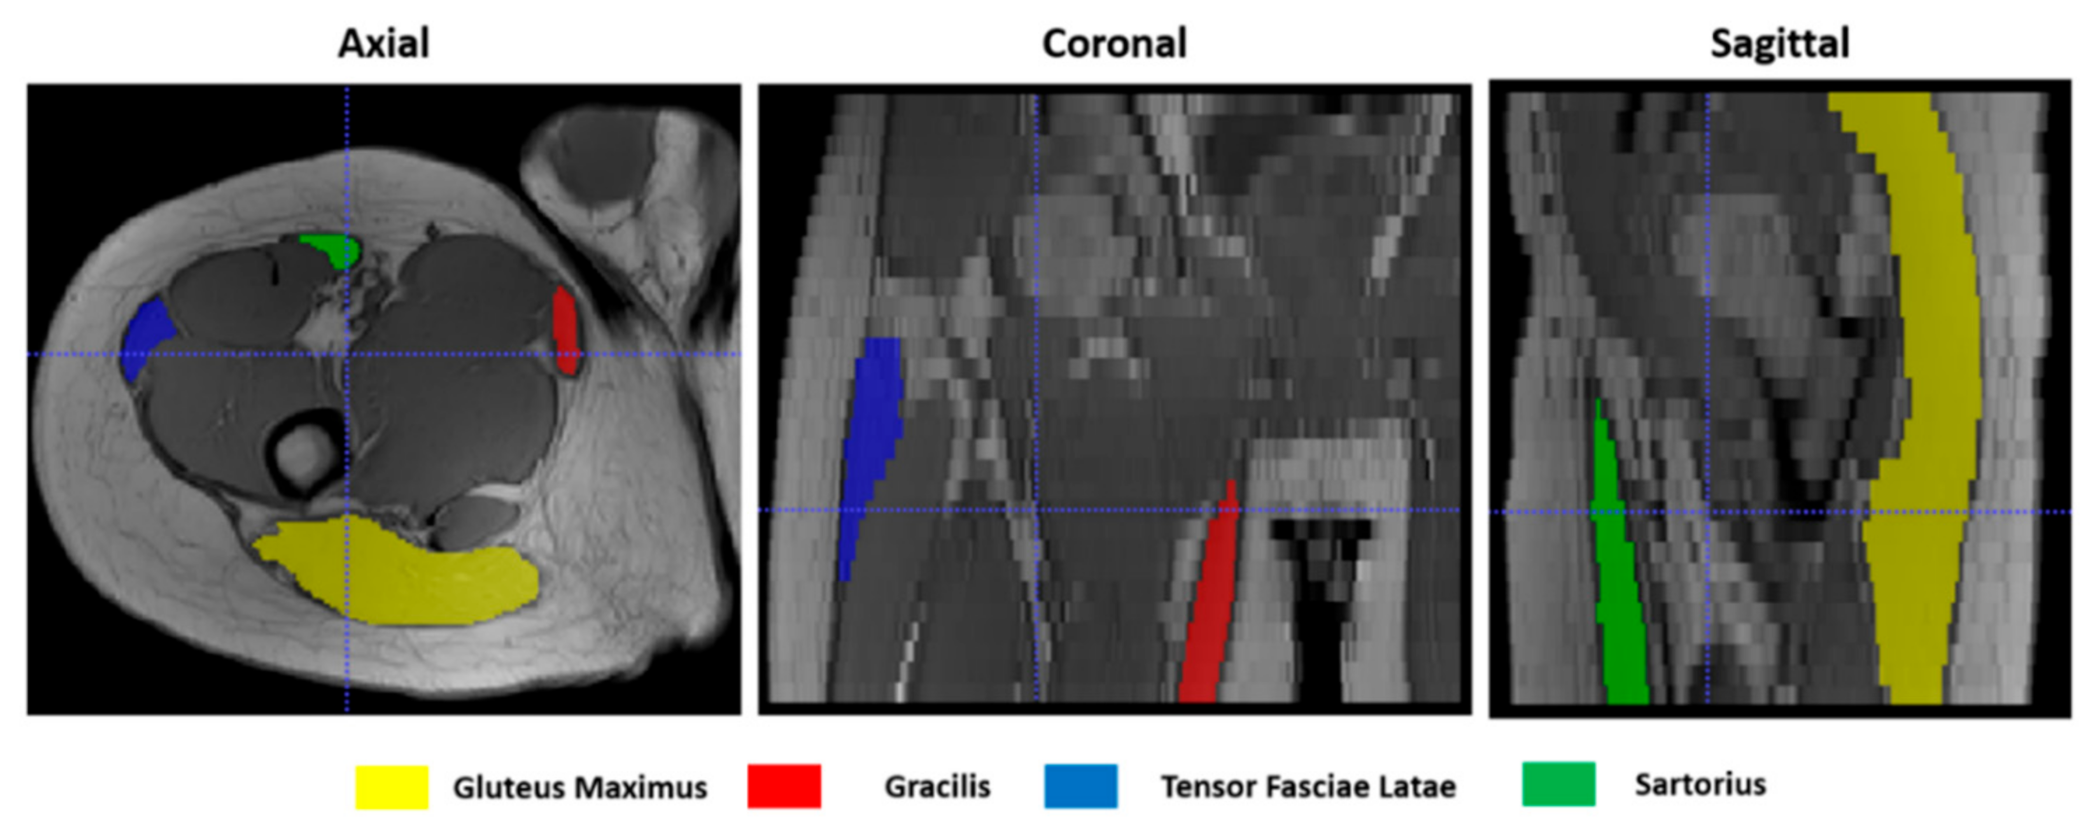

To give a quantitative assessment of the transformation accuracies, the surfaces of 4 representative hip muscles—gracilis, sartorius, gluteus maximus, and tensor fasciae latae—were manually delineated, slice by slice, on the T1w images (Figure 4) at both t0 and t1 separately with ITK-Snap [34]. Region of Interests (ROIs) volumes are listed in Table 1. Contours on t1 were then automatically deformed on the corresponding t0 volumes using the resulting transformation of each registration. Nearest-neighbor interpolation was applied to keep the integer values of the original labels.

Figure 4.

Muscle ROIs delineation on T1-w MR images in 3 orthogonal views.